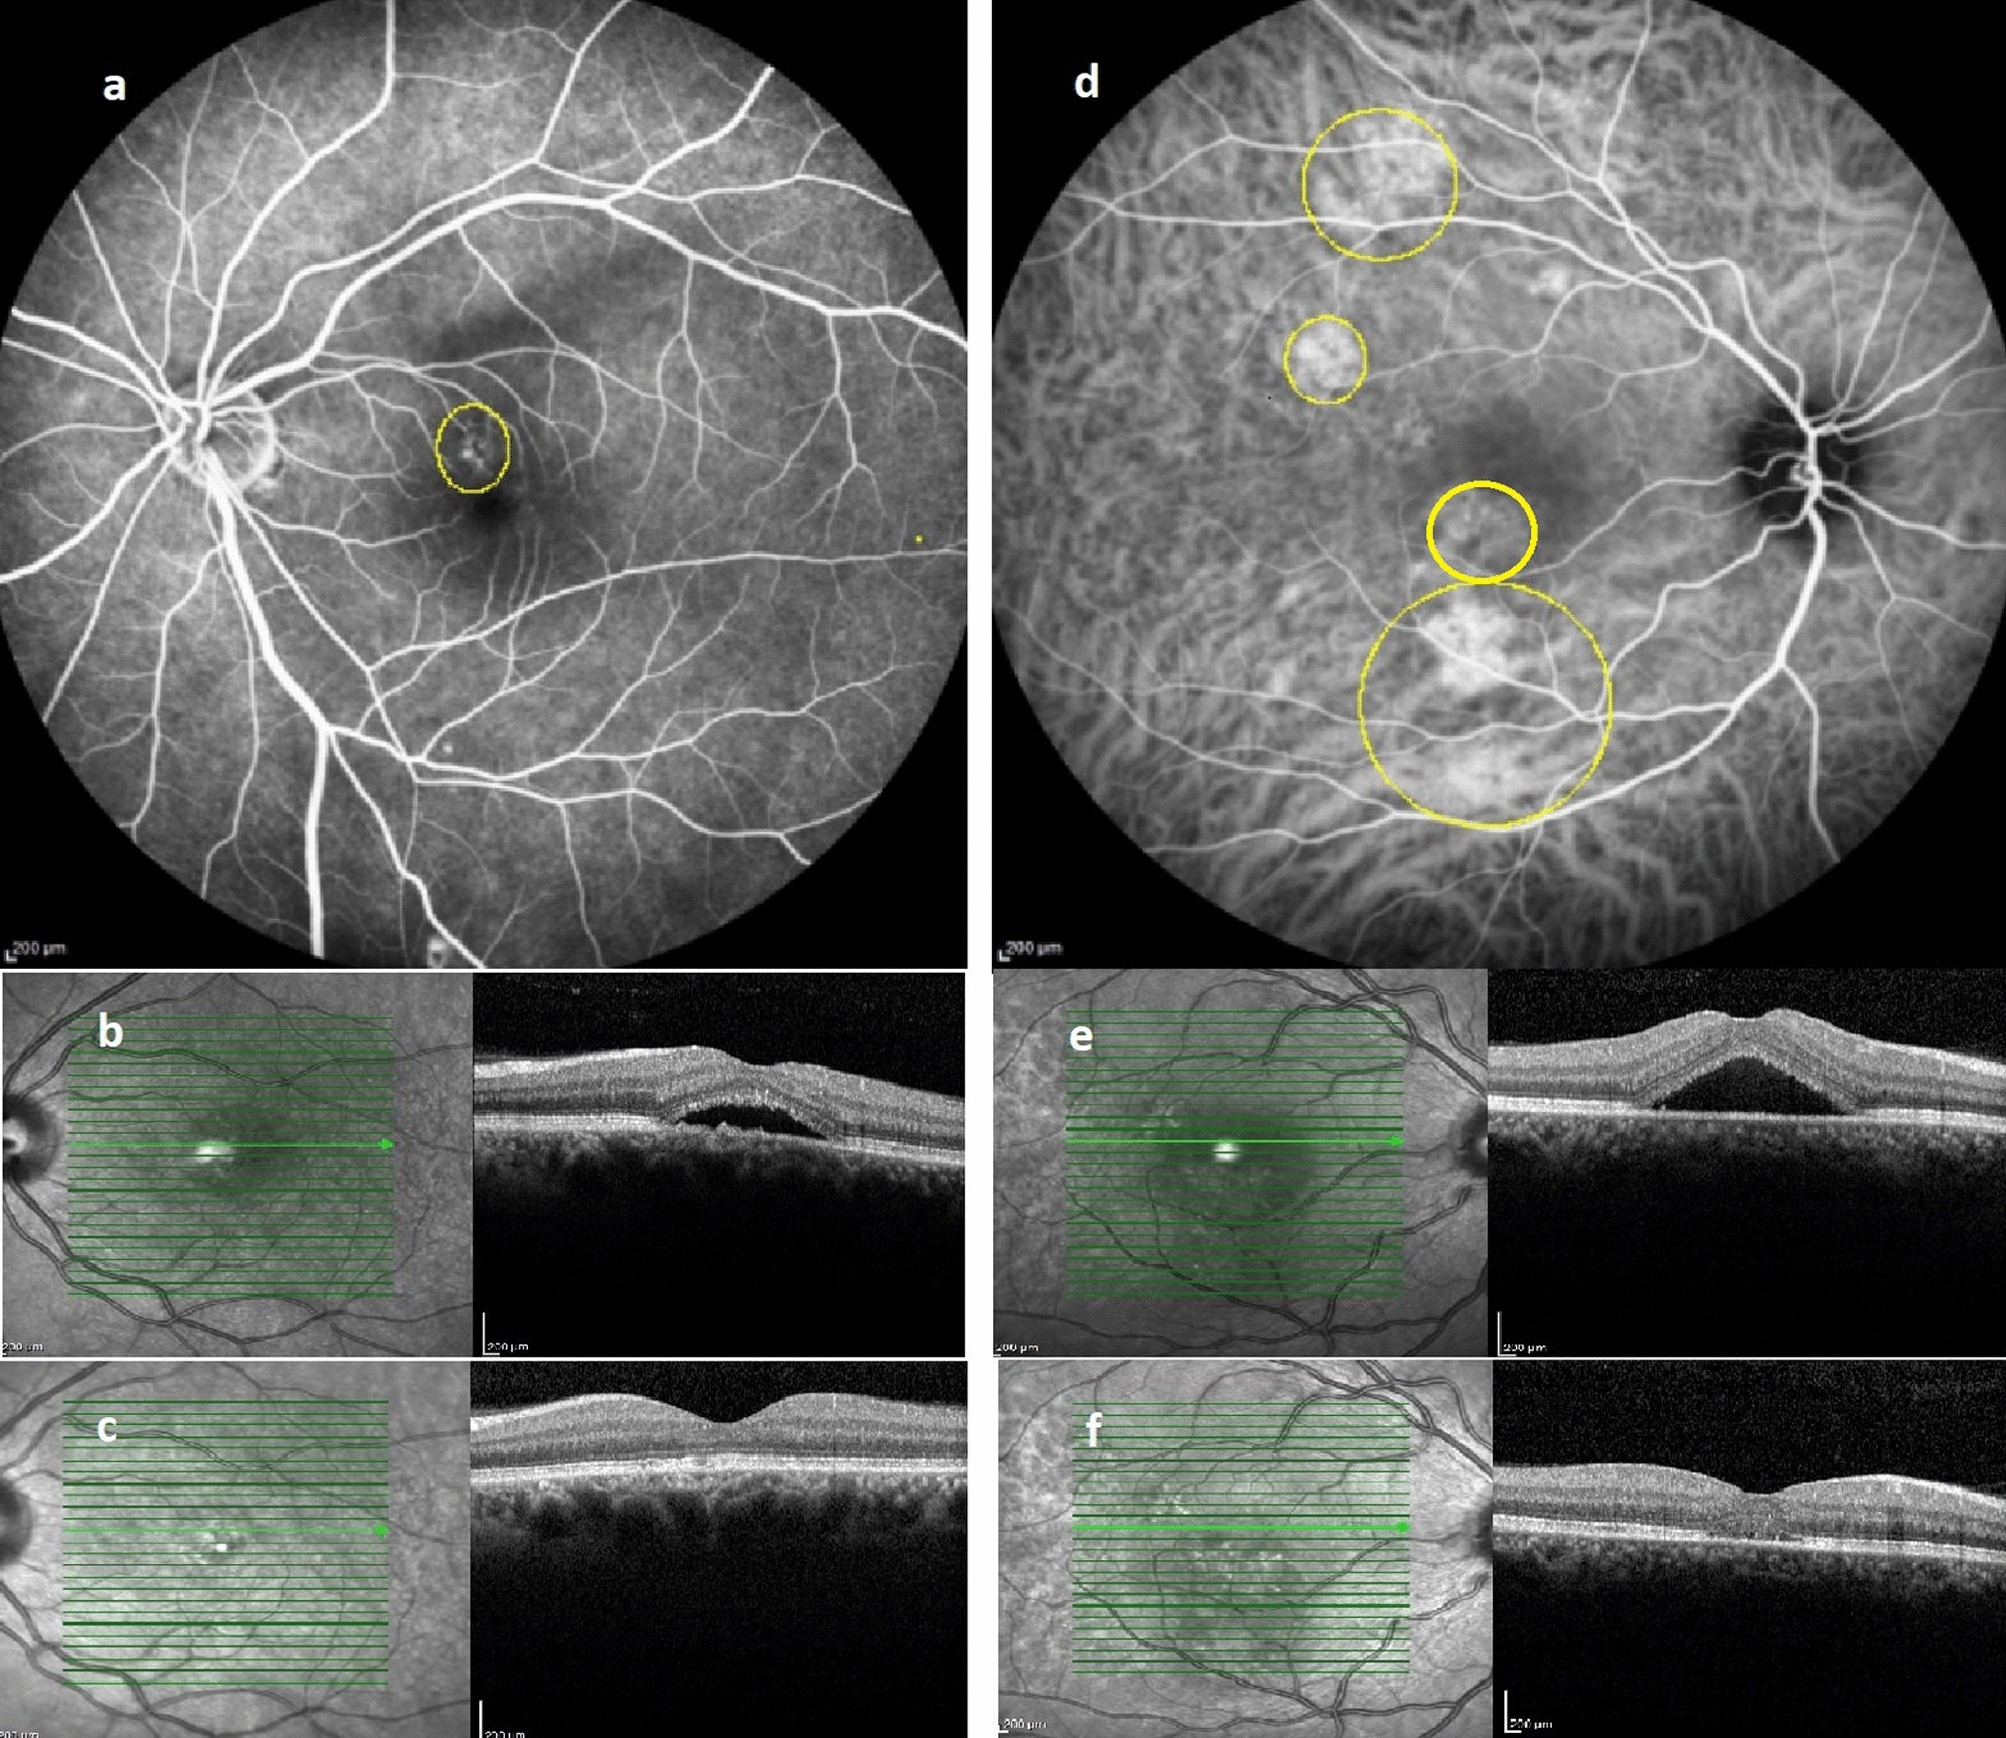

Figure 2

Representative image of patients in FA-based (left column) and ICGA-based (right column) PDT groups: FA; depicted area of leakage was treated with half dose PDT (a). Baseline OCT reveals foveal subretinal fluid (b), which completely resolved following treatment (c). ICGA; delineated areas corresponding to choroidal vascular hyperpermeability received half dose PDT (d). Baseline OCT reveals foveal subretinal fluid (e), which completely resolved following treatment (f).